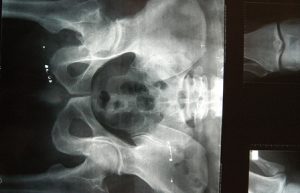

Añadió que aunque puede presentarse en cualquier hueso, la fractura de cadera es la más peligrosa, por ser altamente discapacitante e incluso puede llevar a la muerte, ya que cuatro de cada 10 personas que la sufren, no rebasan el siguiente año de vida a causa de diversas complicaciones como infecciones pulmonares, trombosis y formación de ulceras, por la poca o nula movilidad de quienes quedan postrados en una cama o limitados a una silla de ruedas.

Torres Martínez señaló que al año se presentan alrededor de 21 mil casos de fractura de cadera y que la importancia de atender esta enfermedad lo antes posible, radica en que la población mexicana tiende al envejecimiento.